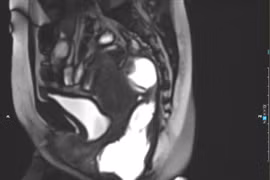

Tiêm búi trĩ không đau người bệnh 35 tuổi biến chứng nặng nề

Tiêm xơ búi trĩ không phải là giải pháp cho mọi trường hợp. Người dân cần chú ý những lời quảng cáo “có cánh” trên mạng để tránh tiền mất tật mang.